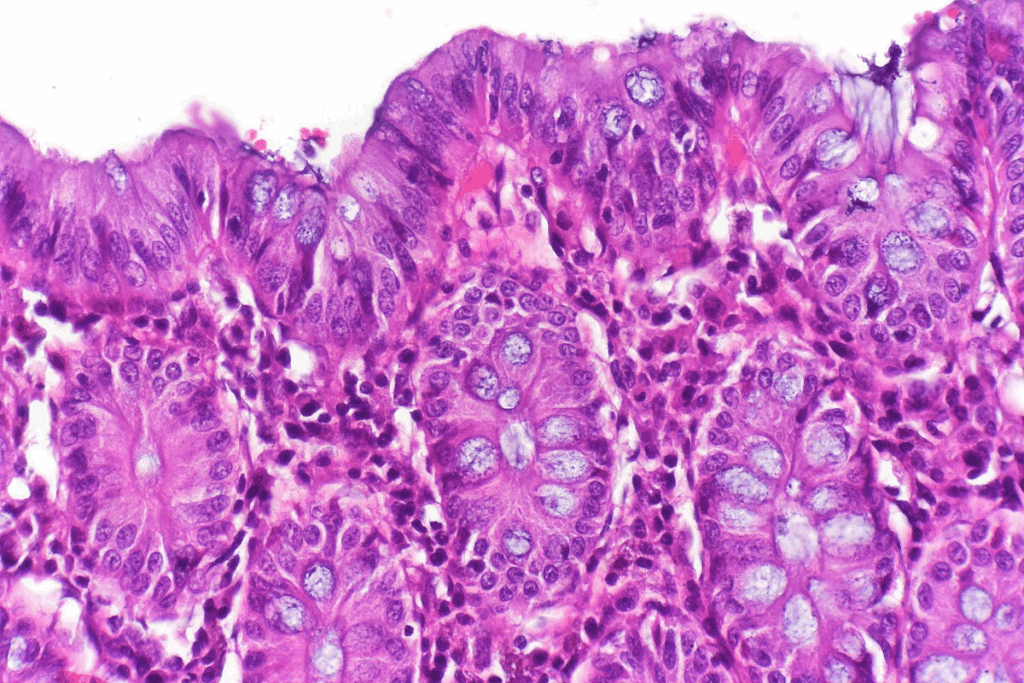

The walls of the small intestine have finger-like projections called villi. These projections help in absorbing nutrients. They are full of blood vessels and special cells that move nutrients into the blood.